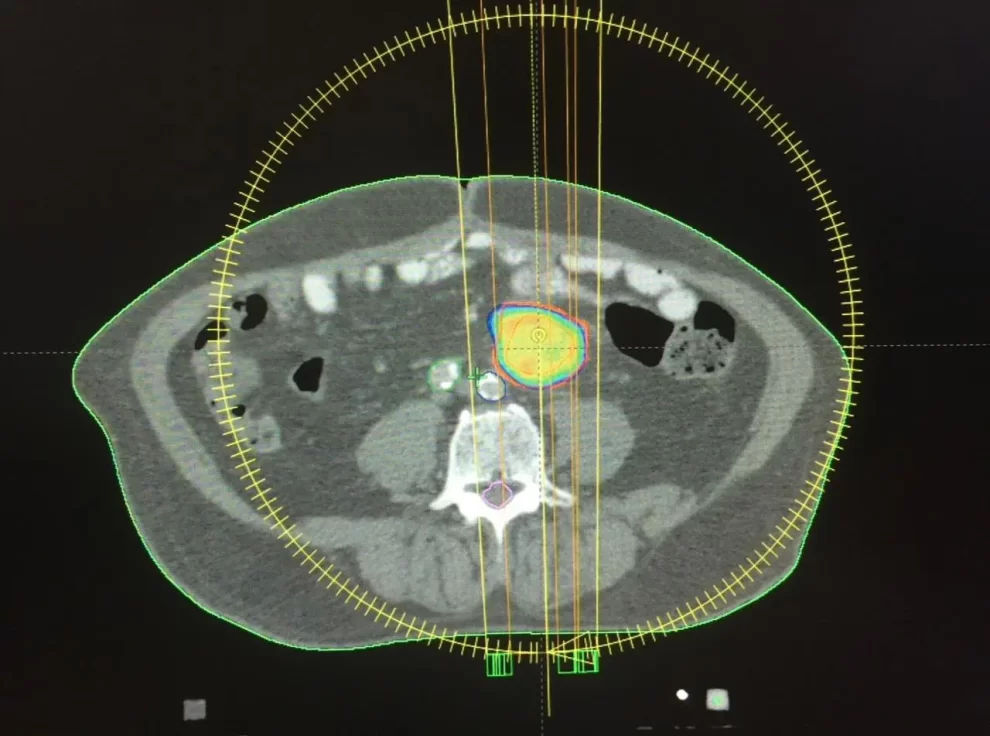

Este método se realizó en pacientes con metástasis primarias en los ganglios linfáticos colorrectales mediante PET-CT y CT abdominal y de pelvis con contraste dual, combinando la dos imágenes y posterior verificación antes del tratamiento, mediante imágenes tomográficas del objetivo a tratar.